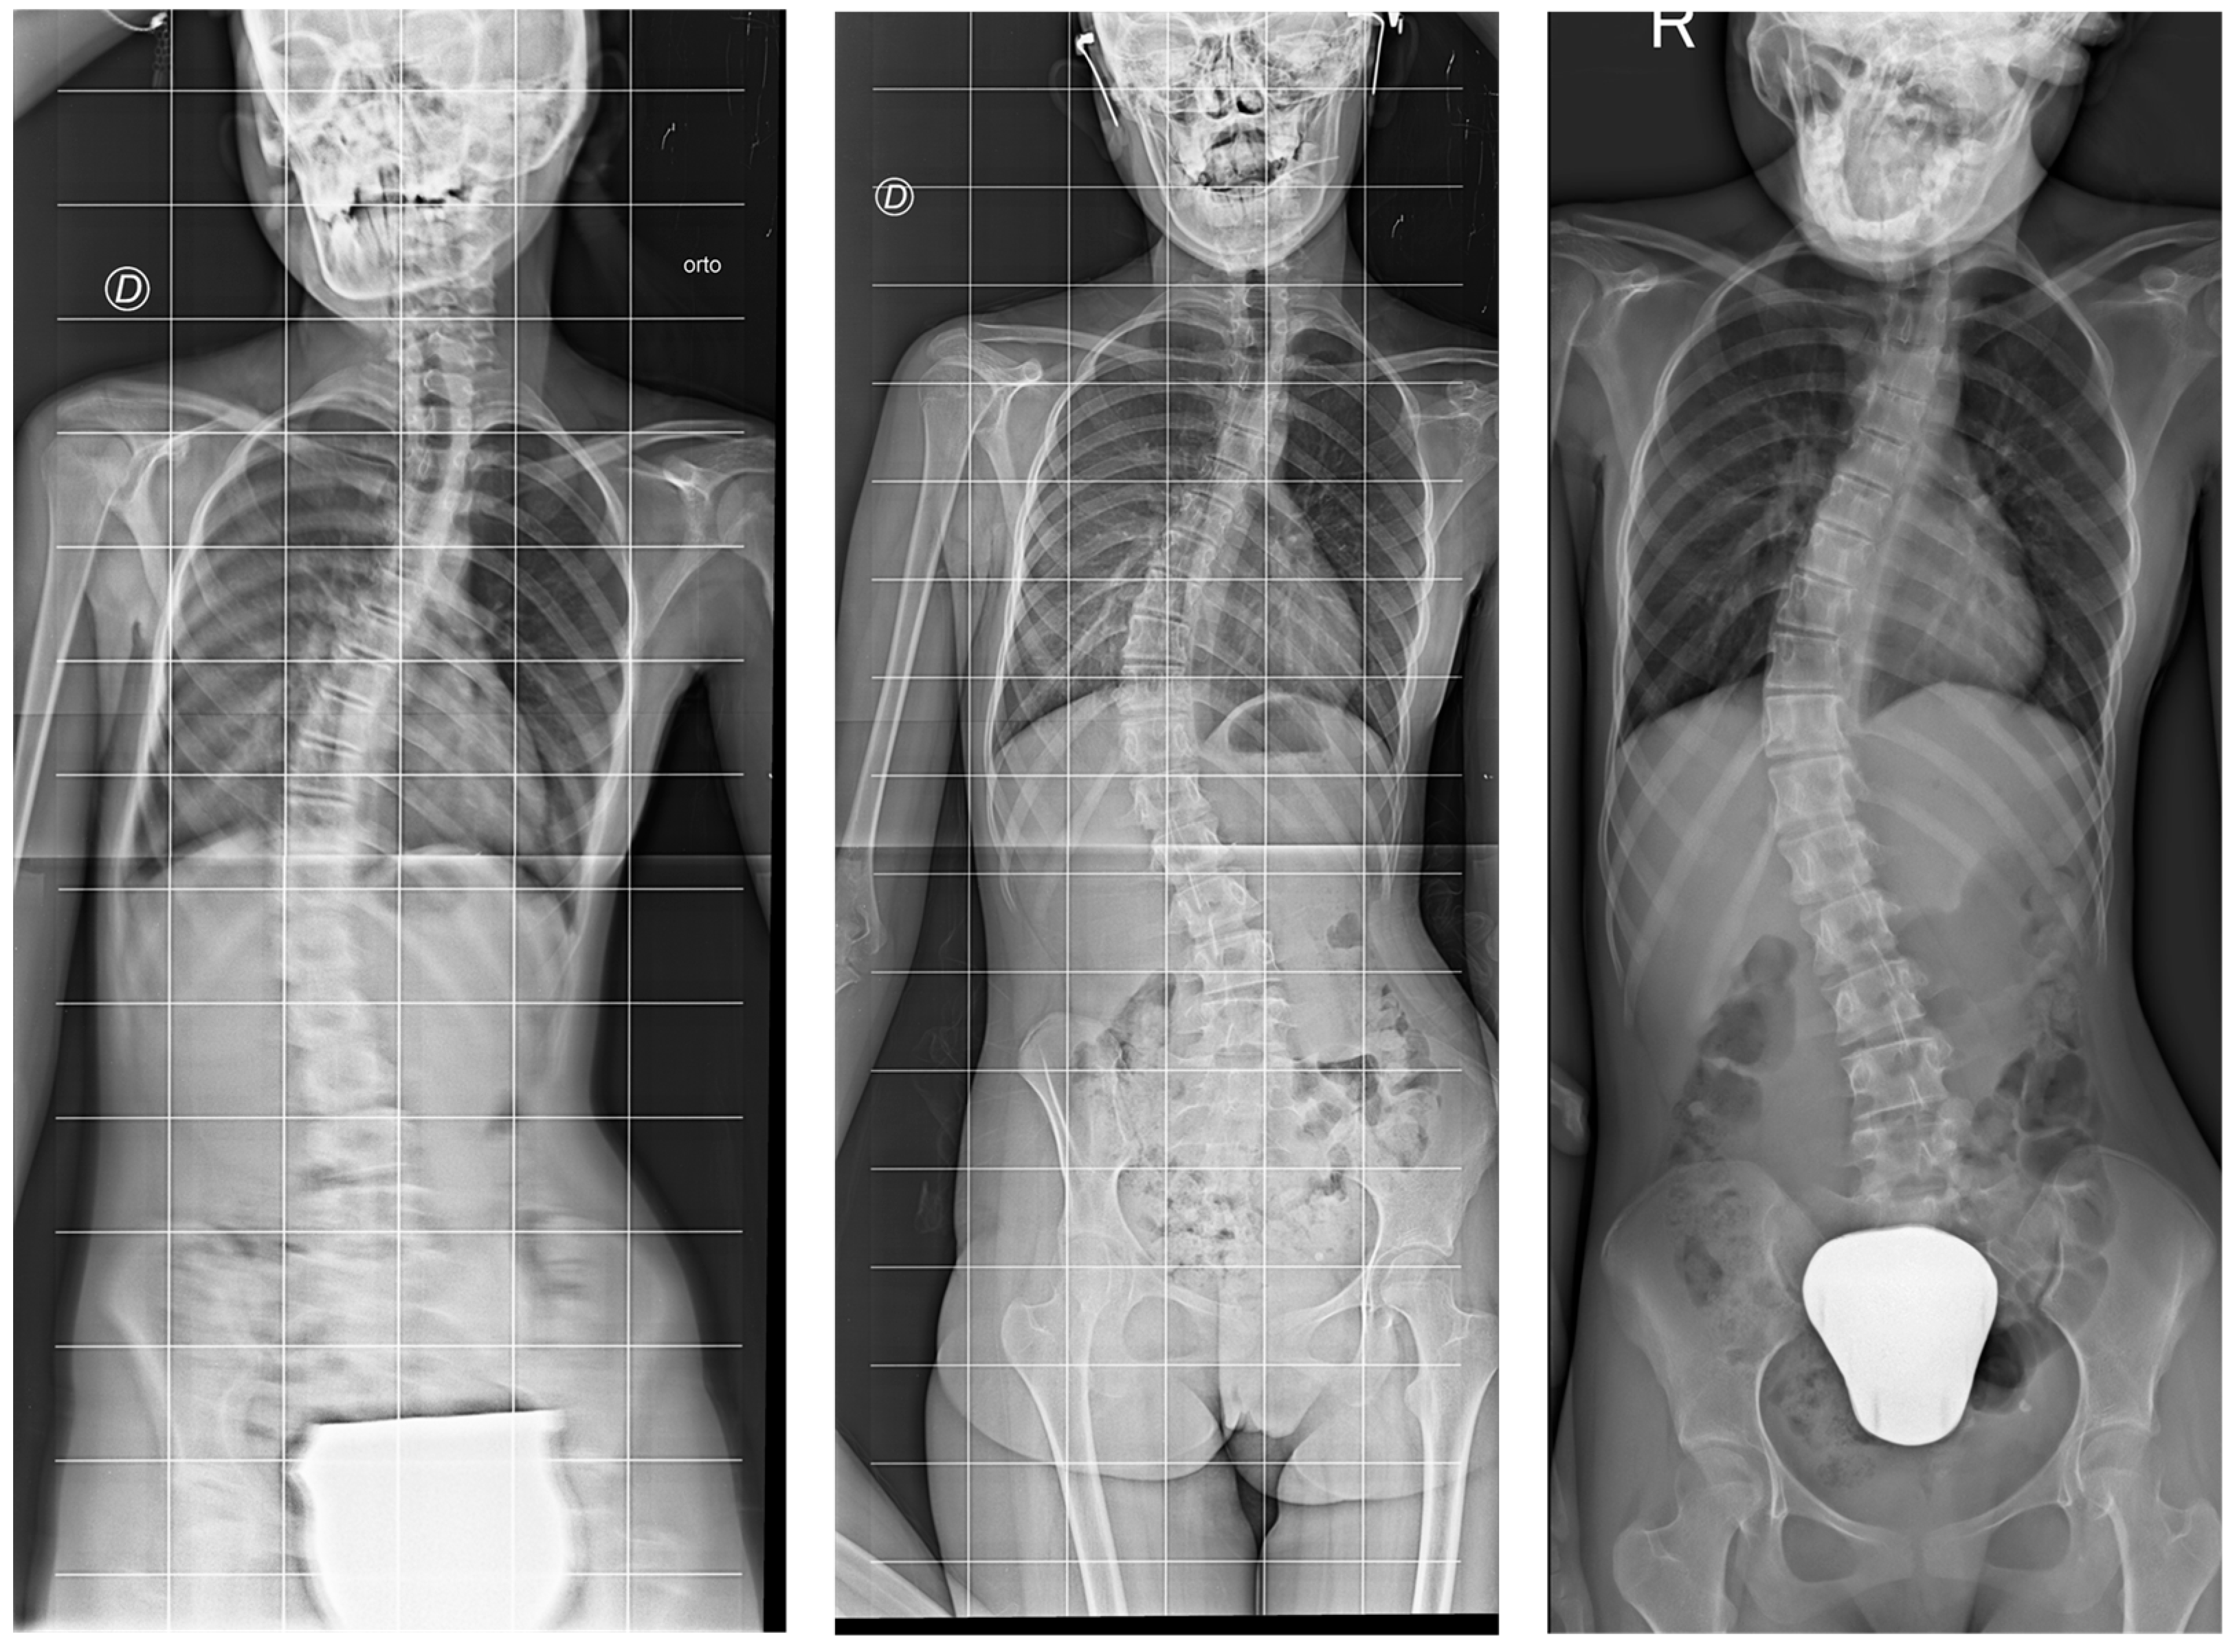

2.3.2. Scoliosis Progression

3.1. Scoliosis Characteristics and Progression

3.2. Individual Responses to Intervention

4.1. Effect of the HEP on Scoliosis Progression